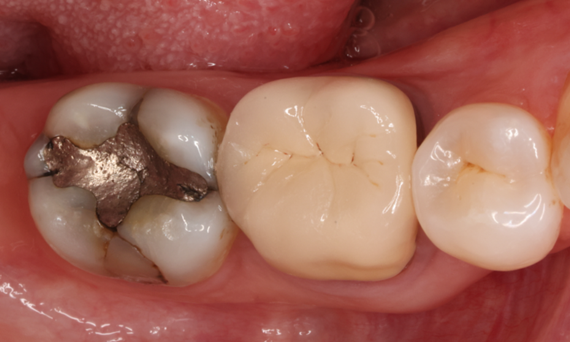

Lower second molar chairside restoration

A partial CEREC Tessera crown

A lower second molar with sensitivity presented with cracks as well as an extensive Class I composite restoration on the buccal surface. According to the minimally invasive concept a CAD/CAM partial crown was planned, fabricated and bonded using CEREC Tessera in a single visit.

Before: Failed amalgam restoration needing replacement. Patient complaining of sensitivity and tooth presenting multiple cracks.

After: Chairside CAD/CAM partial crown restoration fabricated with CEREC Tessera Advanced Lithium-Disilicate glass ceramic.

Dr. Carlos Eduardo Sabrosa

Rio de Janeiro, Brasil